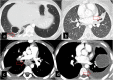

Hydatid cyst caused by the larval form of Echinococcus is a worldwide zoonosis. The lungs and liver are the most common sites involved. While the lung parenchyma is the most common site within the thorax, it may develop in any extrapulmonary region including the pleural cavity, fissures, mediastinum, heart, vascular structures, chest wall, and diaphragm. Imaging plays a pivotal role not only in the diagnosis of hydatid cyst, but also in the visualization of the extent of involvement and complications. The aim of this pictorial review was to comprehensively describe the imaging findings of thoracic hydatid cyst including pulmonary and very unusual extrapulmonary involvements. An outline is also given for the findings of complications and differential diagnosis of thoracic hydatid cyst.